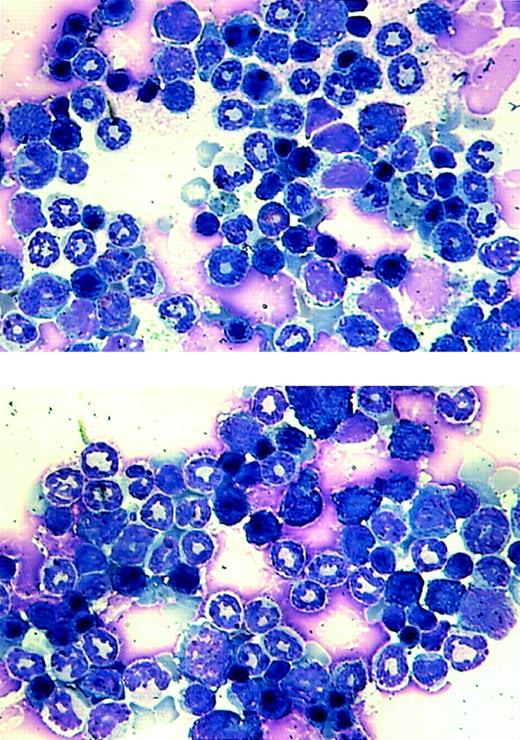

Morphological analysis of bone marrow cells from the transgenic mice.

Bone marrow samples were prepared from a wild-type littermate (top panel) and an MMTV-tTA and pUHD–AML1-ETO double-positive mouse and stained with Wright-Giemsa solution.

Our goal was to investigate the effect of AML1-ETO on hematopoiesis and its potential role in leukemogenesis. Because of the lethal effect of AML1-ETO on embryogenesis, we used the tet-off inducible system of gene expression. We observed adult double-positive mice that express AML1-ETO to study their hematopoiesis. These mice exhibited no outward signs of illness. Their coat appeared normal, and their level of activity was consistent with that of wild-type mice. We performed blood smears and differential counts of the blood from these mice. In all of the founder lines, the differential blood counts were normal (Table 1). We then used bone marrow cells from founder lines #7 and #8 to perform in vitro CFU assays. The numbers of different colonies observed for both double-positive and wild-type mice were approximately the same (Table1). These mice showed no abnormal hematopoiesis. CFU assays were also performed in which cells isolated from the same MMTV-tTA/AML1-ETO double-positive mice were plated in the presence or absence of tetracycline. No difference was observed in number or type of colonies generated (data not shown). Total RNA was then harvested from colonies from the CFU assay for founder line #8 and analyzed by Northern blot analysis. A similar level of AML1-ETO expression is seen in both the bone marrow of double-positive mice and colonies derived from the bone marrow of double-positive mice (Figure6). Bone marrow cells were also analyzed for their morphology (Figure 7). No significant difference can be observed between bone marrow samples from the control and AML1-ETO–expressing mice.